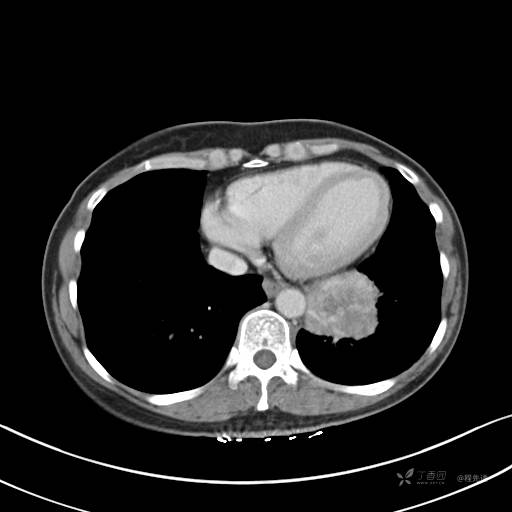

CT平扫

纵隔窗

病灶平扫CT值约31HU